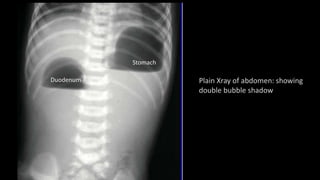

• Plain X ray abdomen : “double-bubble” sign.

Plain Xray of abdomen: showing

double bubble shadow

Stomach

Duodenum